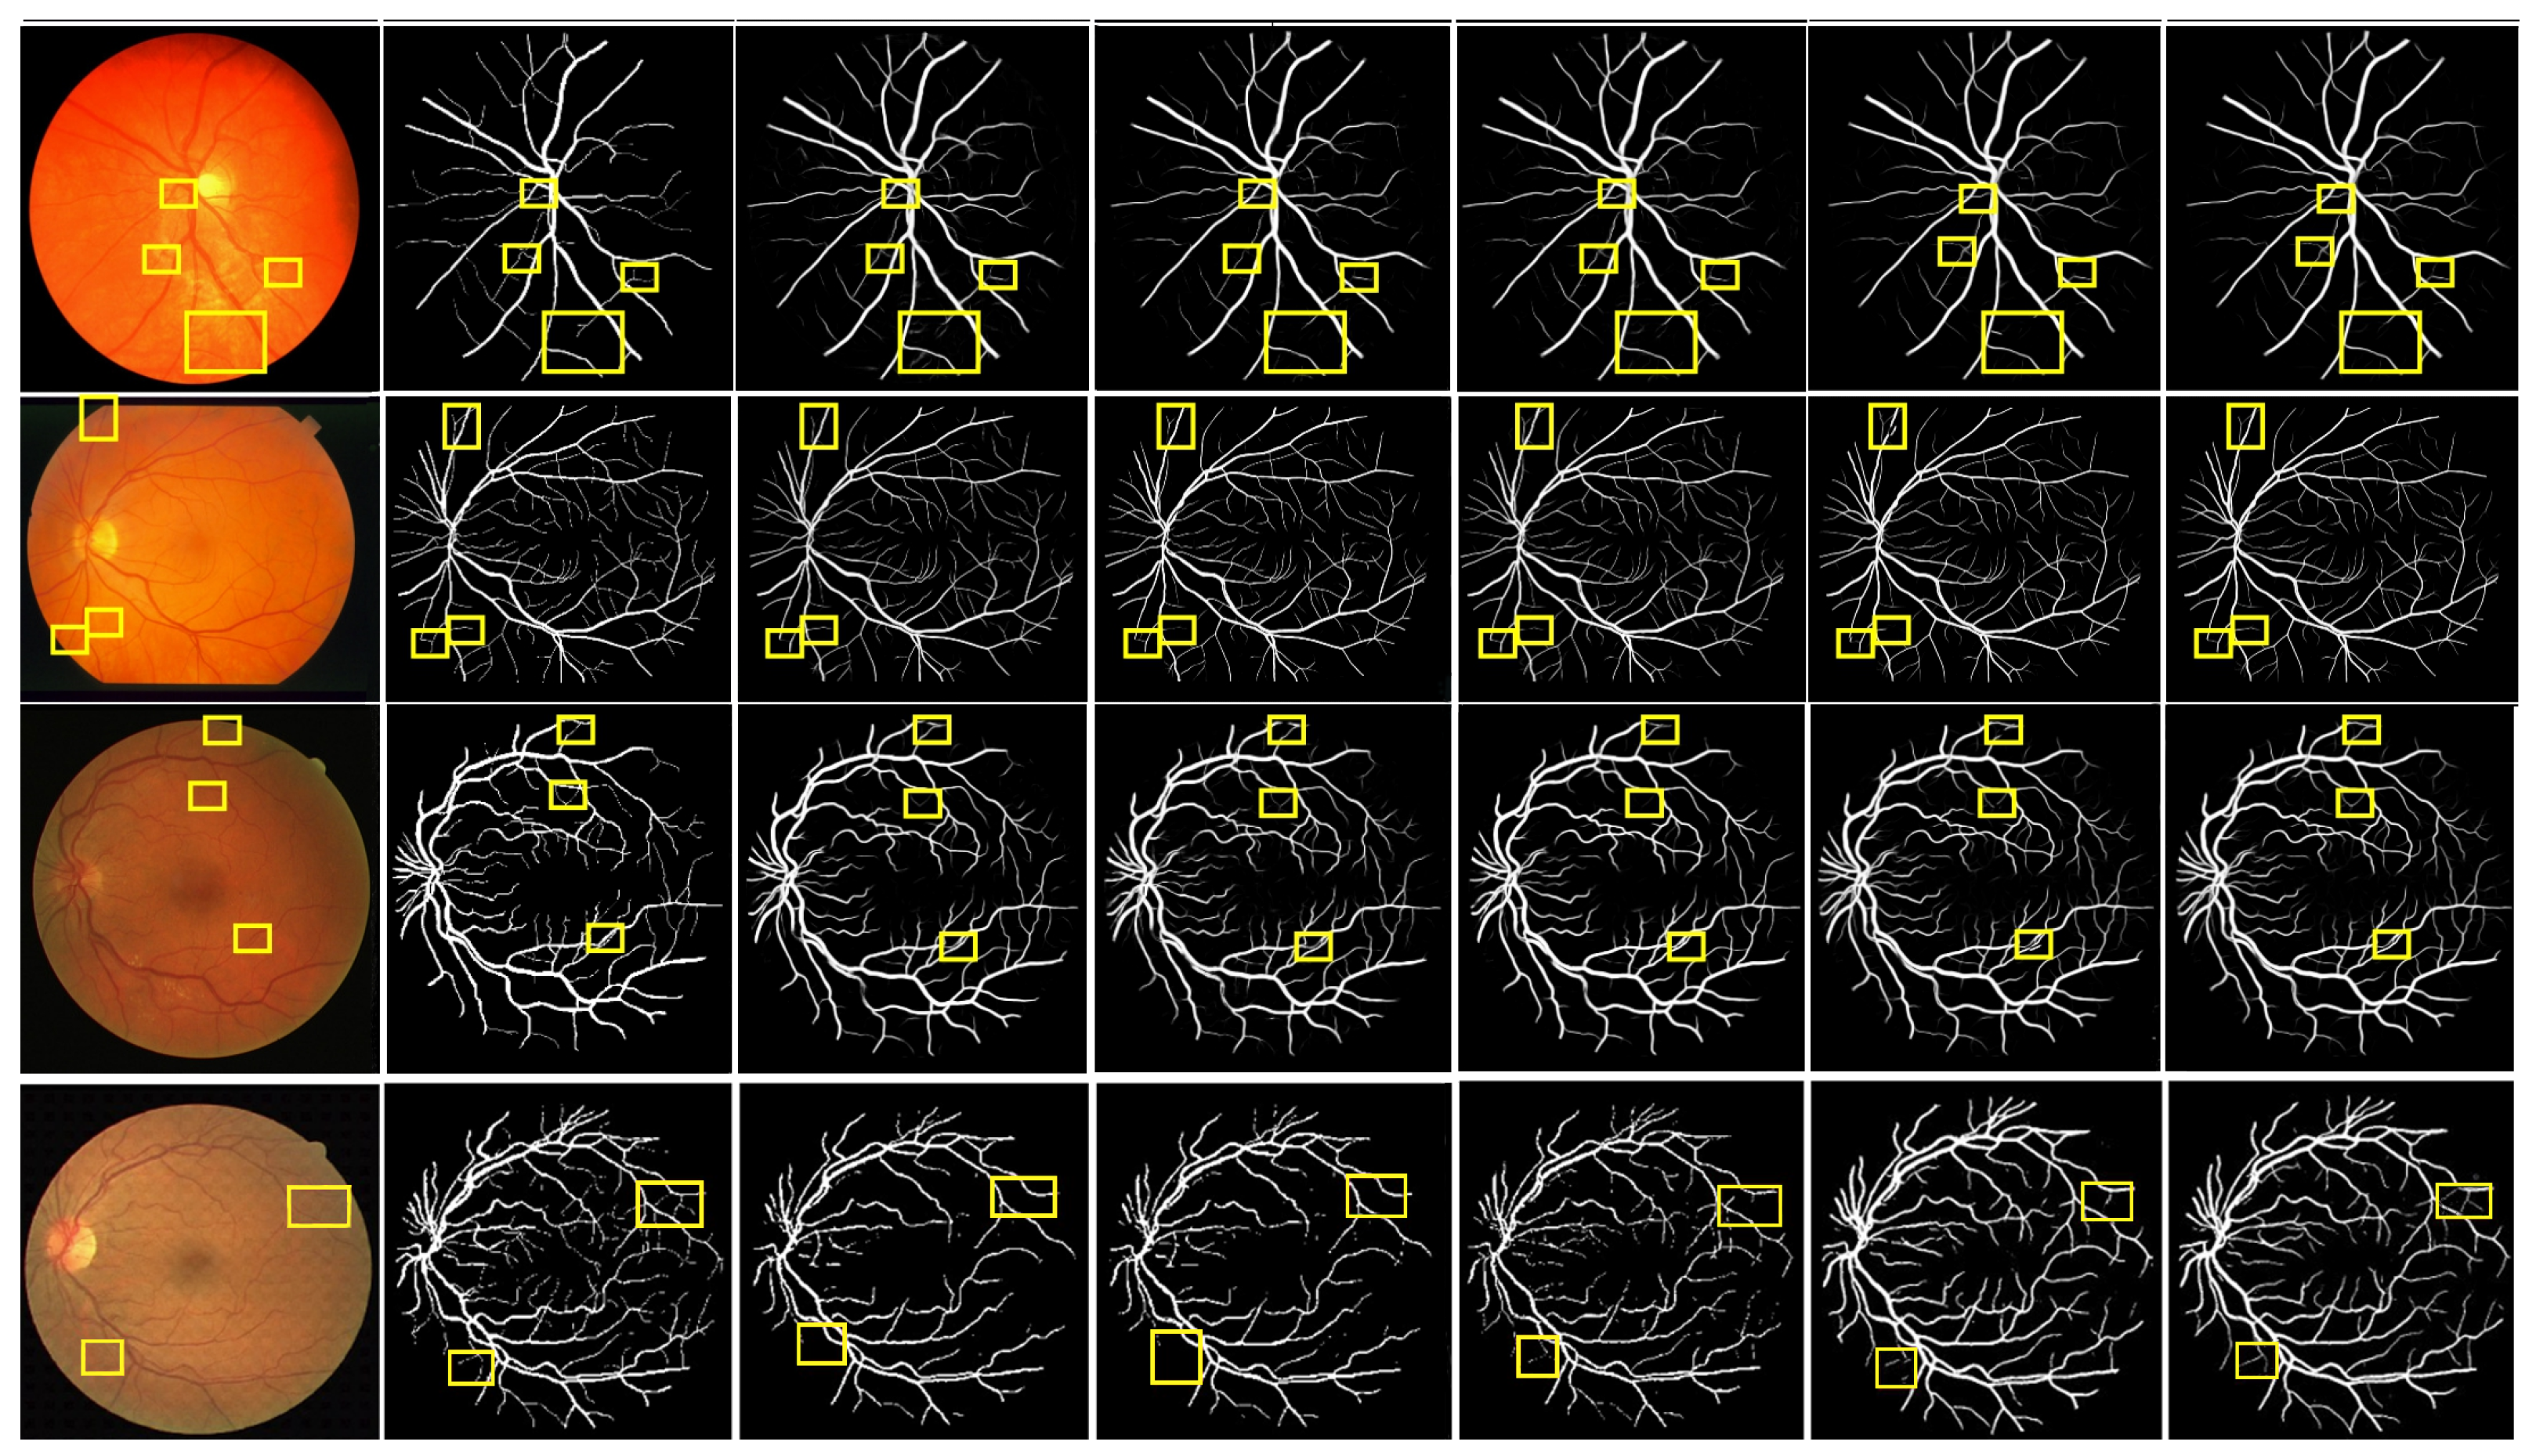

4.6. Qualitative Analysis

To verify the superiority of MPCCN, it was compared with different RVS algorithms, i.e., RVSA [46], ARDC-UNet [62], FAFFN [63], and TCU-NET [64]. The same experimental conditions and training strategies were used to perform RVS experiments on the DRIVE and CHASE_DB1 datasets. The experimental results are shown in Figure 8. From Figure 8 and Figure 9, it can be observed that RVSA [46], as a classic algorithm for RVS, can only segment the general direction and distribution of the vessels. However, it tends to show major vessel breaks and mis-segmentation at vessel intersections.

Building upon the foundation of RVSA [46], ARDC-UNet [62] replaces convolution blocks with residual convolutions. This allows for the fine extraction of the main vessel network without overfitting, thus outperforming the traditional U-Net. Nevertheless, TCU-NET [64] has a low accuracy rate for extracting tiny vessels and tends to produce false positive vessel areas. On the other hand, ARDC-UNet [62] introduces an attention gates mechanism at the skip connections, which helps to suppress noisy background regions while increasing the focus on vessel areas. This mechanism reduces the impact of background noise while extracting the main network, but mis-segmentation still occurs with tiny vessels.

Furthermore, FAFFN [63] introduced parallel channel and spatial attention modules at the bottom of U-Net, unifying local and global vessel information to achieve high-precision vessel segmentation. It can accurately segment both the main and tiny vessels, with high accuracy in tiny vessel segmentation. However, mis-segmentation still occurs at vessel edges. In contrast, the segmentation results of MPCCN are consistent with the manually segmented vessel images by experts. Compared to other algorithms, MPCCN maintains connectivity in tiny vessel segmentation, reduces the impact of background noise, and ensures vessel connectivity. Therefore, MPCCN finely preserves vessel structural information, has a certain degree of anti-interference capability, and achieves high-precision RVS.

To further verify the performance advantage of MPCCN, a local region comparison of segmented images was conducted with RVSA, ARDC-UNet, and FAFFN algorithms. The comparison results are shown in Figure 10. RVSA can segment main vessels but has low segmentation accuracy at vessel intersections and in tiny vessel areas. ARDC-UNet improves the segmentation effect of tiny vessels compared to RVSA, but disconnection often occurs. The FAFFN model can gradually segment the general shape of boundary vessels, but disconnection still occurs. In contrast, MPCCN accurately segments both the main and tiny vessels without disconnection, greatly ensuring the integrity of the segmented retinal vessels. This comparison highlights the strengths of MPCCN as it effectively combines the advantages of the aforementioned methods while minimizing their drawbacks. Through a comparison of the segmentation details of different algorithms, it was demonstrated that replacing traditional convolutions with PCC can retain image contents as much as possible and can effectively highlight key vessel information. Additionally, standard convolution, PCC, and efficient channel attention can expand the receptive field to improve segmentation accuracy, promoting the integration of main and tiny vessels. MIM allows the algorithm to fully utilize encoding information at different levels, helping to eliminate background noise and redundant information in vessel feature maps. These results verify that MPCCN has high accuracy and anti-interference capability in RVS.